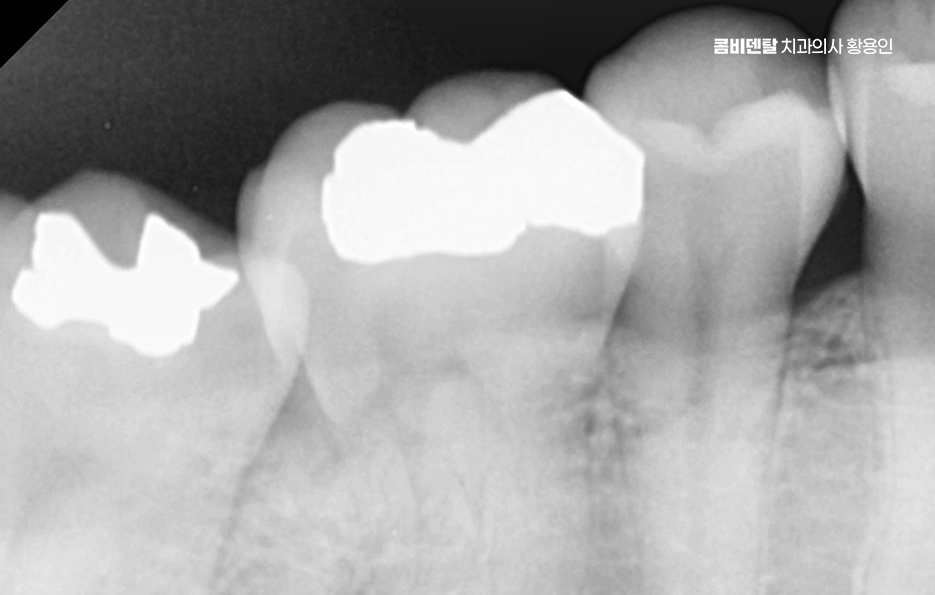

처음엔 안 보일 정도의 크랙이 생기고, 그 사이로 음식물과 세균이 침투하면서 2차 충치가 생기기 쉬운 것이며 특히 어금니처럼 씹는 힘이 센 부위에 들어간 아말감은 이런 팽창으로 인해 치아에 미세한 금을 만들고, 결국은 깨지거나 뿌리까지 손상이 가는 일이 생길 수 있기 때문에 늦지 않게 아말감 교체 레진 같은 재료로 재치료를 고려해야 할 수 있었어요

다음으로 아말감은 경계 부식이 문제가 될 수 있는데 접착력이 비교적 약한 편이라 시간이 지나면 테두리가 들뜨거나, 잇몸과의 접촉면에 틈이 생길 수 있고 이 틈은 결국 충치가 다시 생길 수 있는 통로가 될 수 있으며 아말감 아래쪽에 숨어서 진행되는 충치는 눈에 잘 띄지 않아서 발견이 늦어지는 경우가 많아서 나중에 발견되었을 땐 이미 신경까지 번져 있는 경우도 많이 있었어요

이런 아말감 부작용들이 의심되는 경우에는 조기에 제거하고 재치료 계획을 세우는 게 좋은데 재치료 방법은 크게 세 가지로 나뉘며 레진, 인레이, 크라운 순으로 치아의 손상 정도와 위치, 그리고 미용적인 요소를 종합해서 결정하는 거예요.

인레이는 치아 내부에 맞춰 제작하는 보철물로 직접 입 안에서 채우는 레진과는 달리, 치아 모양을 정밀하게 본을 뜬 다음, 맞춤형 보철물을 제작해서 접착하는 방식이며 크라운은 치아 전체를 덮는 방식인데 아말감으로 인한 미세 금이 생겼거나, 치아가 이미 깨져서 구조적으로 약해졌다면 크라운이 필요한 것이고 신경치료까지 이어질 수 있다면 크라운 치료로 이어질 수 있기 때문에 아말감으로 인한 재치료 시에는 기존의 잔존 치아를 되도록 잘 보존하는 것이 비교적 간단한 치료로 끝날 수 있는 방법이 될 수 있었어요